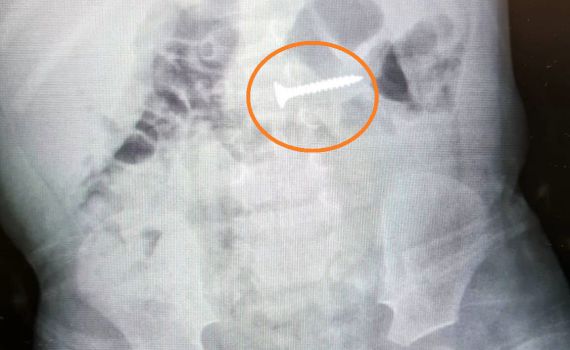

"בצילום רנטגן ראינו בקיבה בורג. כשפעוט בולע גוף זר וחד, מדובר במצב חירום שמחייב פעולת הוצאה מידית. חייבים להוציא את הגוף הזר במהירות לפני שעובר את הקיבה מאחר והבורג עלול היה להיתקע במעי ואף לגרום לחור בדופן המעי. מצב שיכול לגרום לסיבוכים קשים ומסכני חיים " הסביר ד"ר אבי און, מנהל מכון גסטרו ילדים, במרכז הרפואי.

בחדר ניתוח, ד"ר און שלף את הבורג מהתריסריון של הפעוט בשיטה אנדוסקופית ותחת הרדמה כללית: "הצלחנו לאתר את הבורג ולשלוף אותו מהתריסריון , כלומר הוא כבר הספיק לעשות את הדרך לעבר המעיים. לשמחתנו, יום למחרת הפעולה, הפעוט כבר חש בטוב, אכל ושתה ויכולנו לשחרר אותו לביתו".